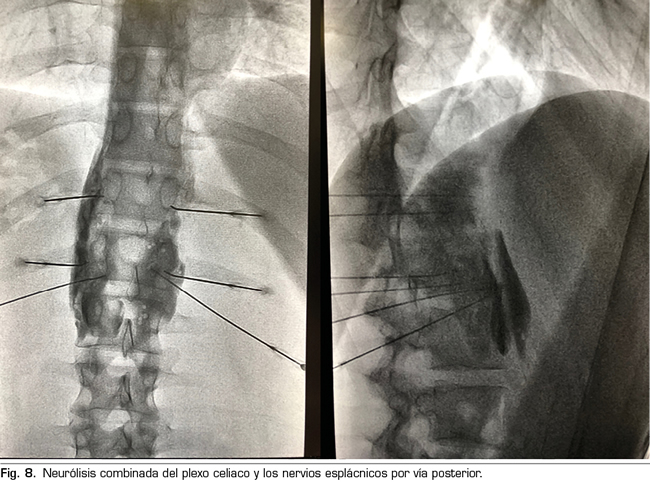

El procedimiento estándar sería el abordaje posterior del plexo celiaco (abordaje clásico), ya que a día de hoy continúa siendo el de mayor evidencia científica, preferiblemente transcrural y guiado por fluoroscopia, debido a su sencillez y rapidez. La ecoendoscopia estaría indicada para la neurólisis aprovechando su indicación diagnóstica o terapéutica, para situaciones de imposibilidad para el decúbito prono, y como alternativa en caso de que falle el abordaje posterior. La neurólisis percutánea ecográfica quedaría reservada para casos seleccionados, dependiendo de la experiencia del operador, ya que es la técnica que menos publicaciones tiene hasta la fecha. Confiamos en que en un futuro se publiquen trabajos que permitan a las técnicas ecoguiadas, ya sean percutáneas o ecoendoscópicas, ocupar el puesto de “método de referencia”, ya que permiten la visualización de las estructuras circundantes con control de la inyección en tiempo real. Una alternativa al bloqueo del plexo celiaco es la radiofrecuencia convencional de los nervios esplácnicos, indicada cuando existe infiltración tumoral del tronco celiaco, alteraciones anatómicas importantes o si fracasa la neurólisis del plexo celiaco. También es posible considerar una neurólisis combinada —bloqueo neurolítico del plexo celiaco asociado a bloqueo neurolítico o radiofrecuencia de los nervios esplácnicos—, como refleja el trabajo de Marra y cols. (60), y como venimos realizando en nuestra práctica clínica habitual en HM hospitales, con el objetivo de aumentar la tasa de éxito y la duración de la analgesia sin aumentar la incidencia de complicaciones, pero hasta ahora no hay trabajos comparativos suficientes para apoyar esta hipótesis (Figura 8).